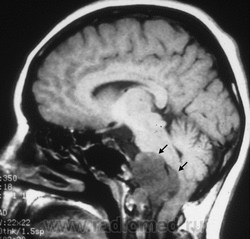

ID: 12796 Chordoma Dr Frank Gaillard - 11 Jan 2011 Although chordomas are typically seen in young adults they need to be co...

ID: 5269 Chordoma - mainly anterior growth Dr Frank Gaillard - 29 Dec 2008 MRI through the base of skull demonstrates a large midline mass centred ...